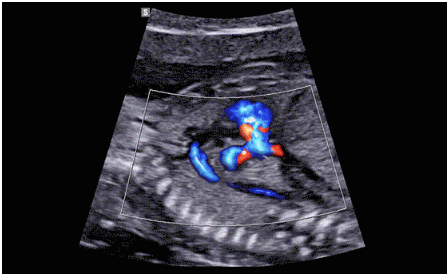

最后,展示一下該機型可搭載的探頭~目前該產(chǎn)品三星本土韓文官網(wǎng)尚未展示,僅能在英文網(wǎng)站查到有關(guān)信息,不知何時才能進入中國呢?